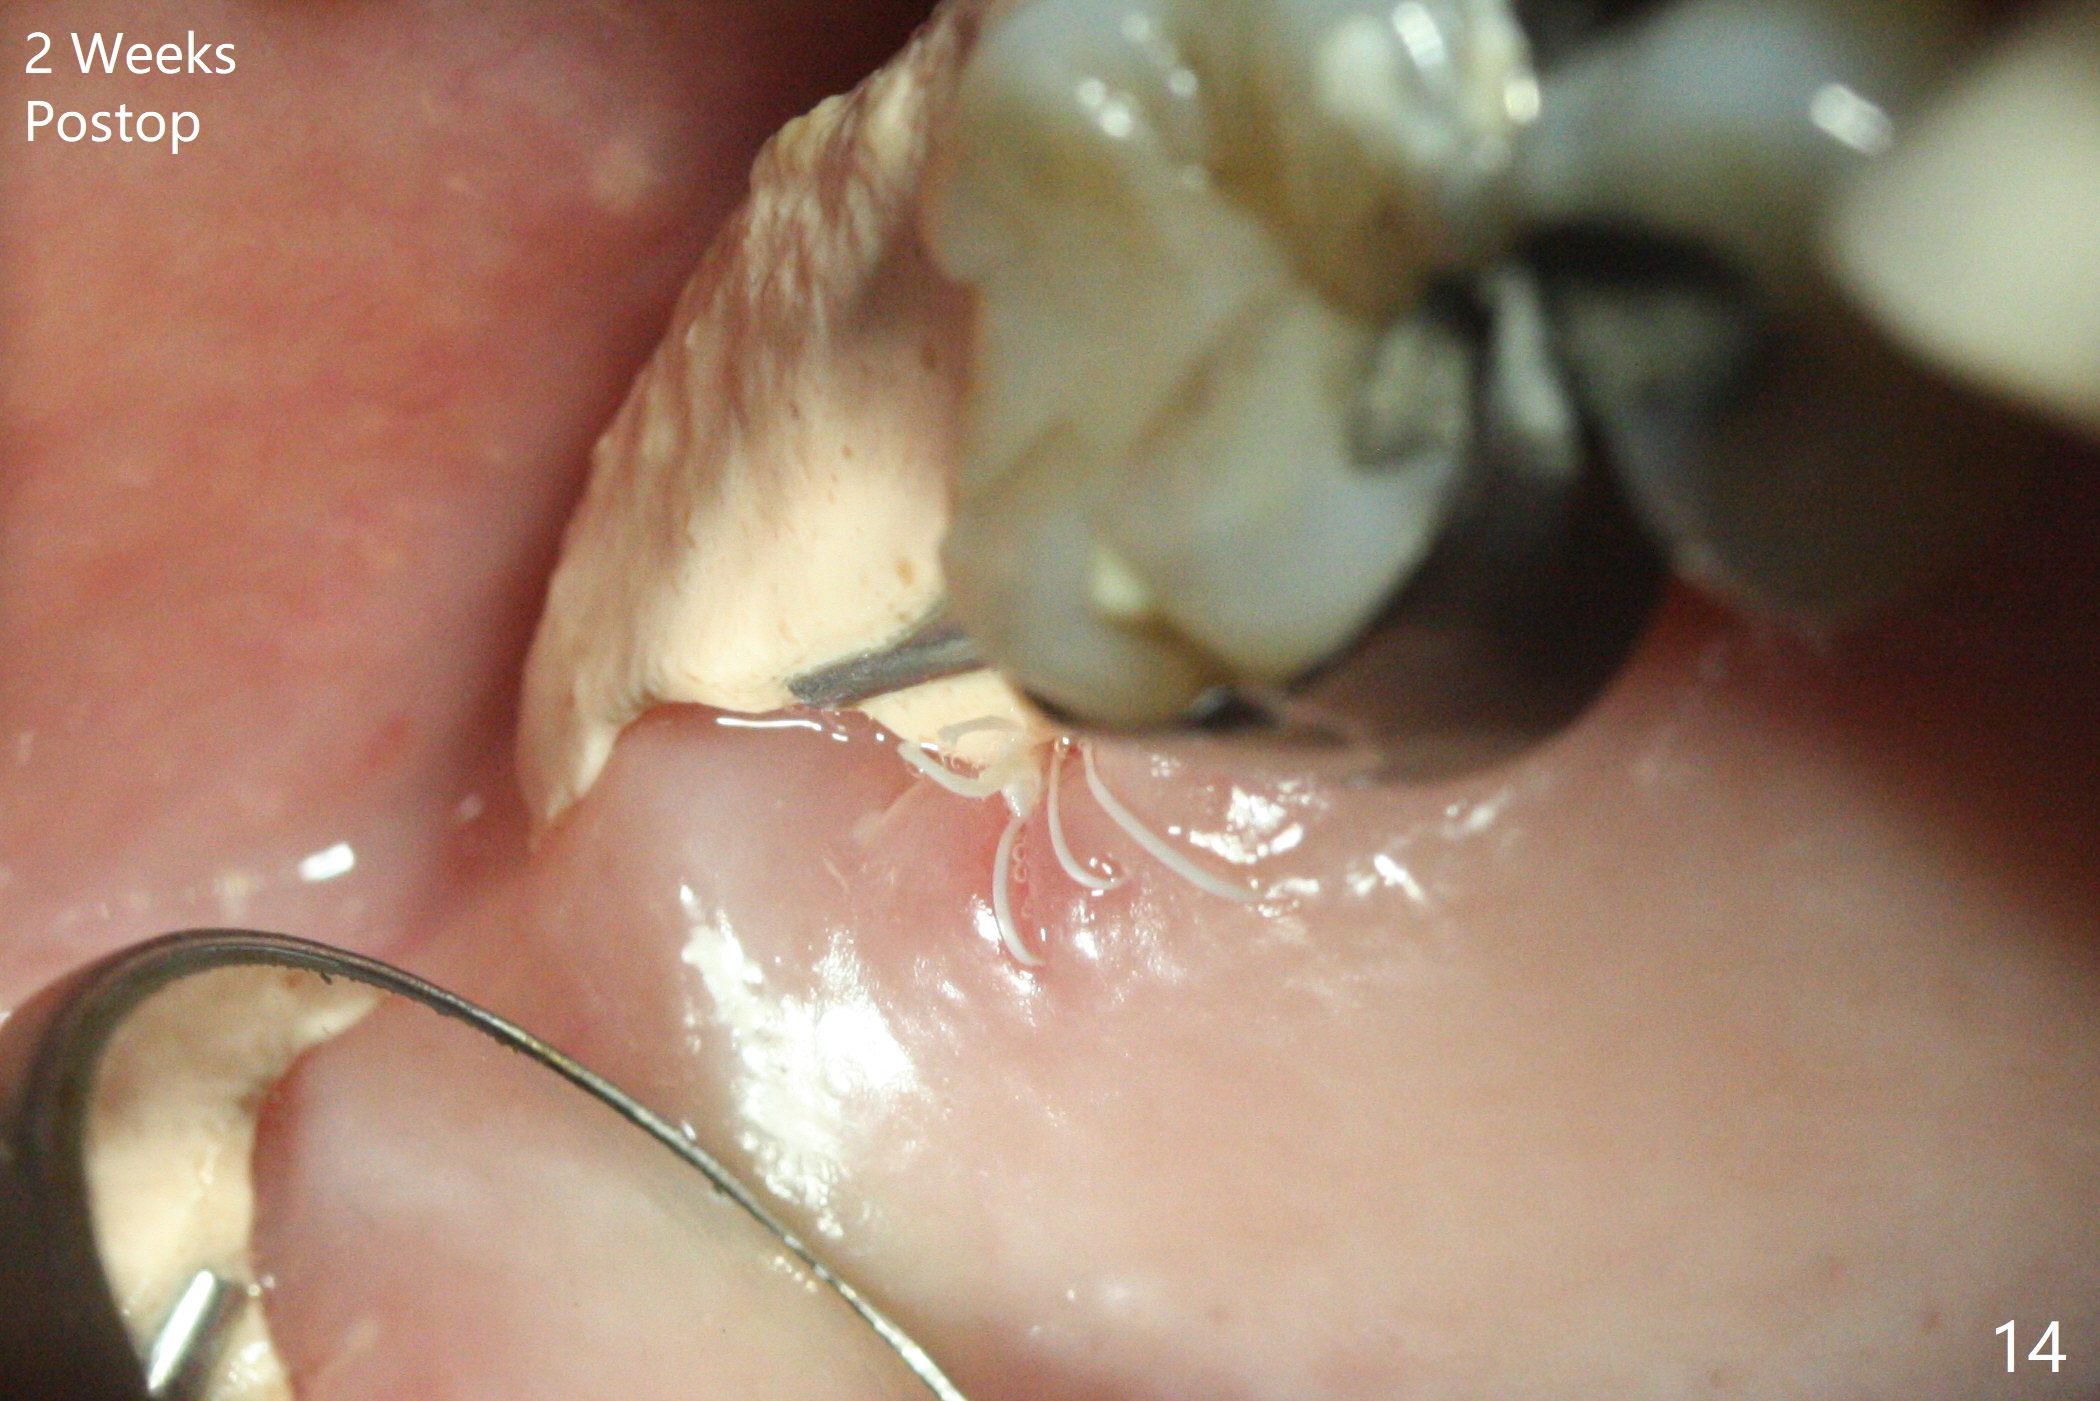

第二磨牙位点保留后,牙周敷料容易脱落,尤其上颌,本文介绍一种方法增加固位。右上七严重牙髓牙周综合征,拔出后使用刮匙除去骨面肉芽组织,颊侧骨板缺失,附着在颊侧粘骨膜上的肉芽组织使用一种叫Stieglitz angled, diamond splinter forceps (德国产,图一,二)撕下来。彻底清除炎性组织必须多次刮治,之间塞入带有灭滴灵(图三:粉剂)和1比50,000肾上腺素局麻药纱布(图四)止血,取出纱布,牙槽窝视野好,继续去除残余的肉芽组织。牙槽窝底部穿孔,用无齿刮匙稍微扩大穿孔后,使用图五下面小的骨粉输送器,将少量骨粉(粘性)送到穿孔处,推入上颌窦(图七:S),之后使用大的骨粉输送器(图五上面),把大量骨粉送到牙槽窝,使用图六上面大的,长的充填器,压实骨粉(图七),骨粉表面放置PRF膜和不可吸收膜(图八),在第一磨牙时安置粘固一个间隙维持器(图九,十),最后铺上牙周敷料(图十一),检查咬合空间,没有干扰。There are sign and symptom of sinusitis 1 week postop; large amount of bone graft retains in the socket by the periodontal dressing and spacer (Fig.12). The sinus membrane (Fig.7 immediate postop) thickens 1 week postop (Fig.13). Augmentin and Medrol Dose Pak are prescribed. 上颌窦炎一周后消失,腭侧牙周敷料丢失,伤口好像正常愈合(图十四)。术后三周牙周敷料由于大量水枪冲洗脱落(图十五)。因为病人需要离城两个月,间隙保持器撤除(图十六),不可吸收膜腭侧稍微外翻 (<),可能有利于术后五周自行脱落。No Deviation SP 下一个病例 位点保留后Xin 导板与张口度 第一磨牙即种 Wei, DDS, PhD, MS 1st edition 09/17/2020, last revision 04/30/2021